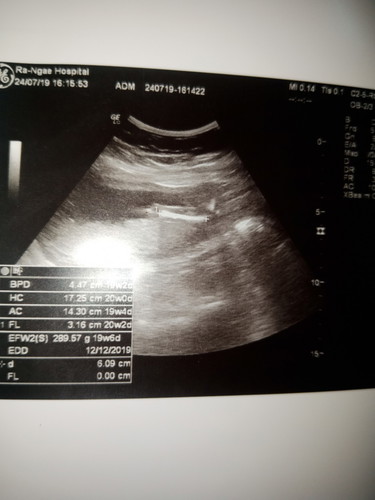

คือเราจำประจำเดือนล่าสุดไม่ได้เลยบอกที่อนามัยว่าหมดล่าสุดน่าจะปลายเดือนมีนา แล้วเค้าก็บอกว่าตอนนี้เรา 17 วีคแล้ว กำหนดครอดเราประมาณวันที่ 02/01/63 แล้ววันนี้เรามีนัดซาวที่โรงพยาบาล แล้วผลซาวออกมาว่าเรา 19+6 แล้ว กำหนดครอดตามใบซาว คือ 12/12/62 เราควรยึดอันไหนเป็นหลักดีค่ะ ขอบคุณสำหรับคำแนะนำคะ ??